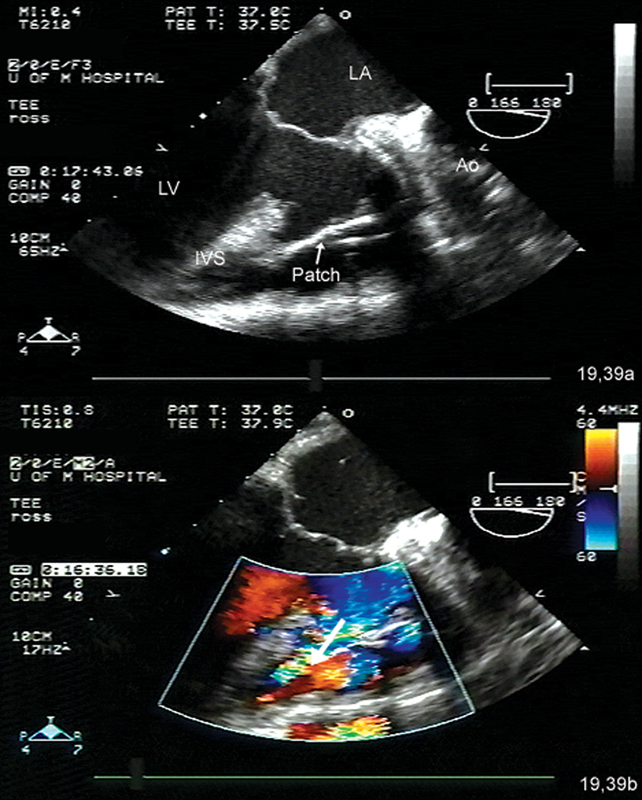

فحوصات تشخيصية لبعض امراض القلب والشرايين التاجية